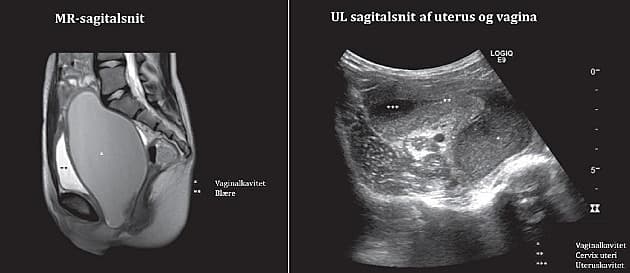

En 13-årig pige med nedre mavesmerter og urinretention.

Ultralydskanning gav mistanke om hæmatokolpos, som blev bekræftet ved MR-skanning. Årsagen var hymen imperforatus.